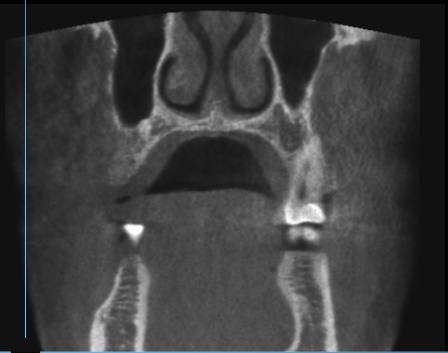

Пропила 2 курса антибиотиков. Хирург сказал, что все зубы в порядке, и отправил домой нервы лечить. Рентгенолог увидела повреждения и сказала не есть больной стороной и вообще не жевать. Это избавило меня от постоянной боли. Но стоит только дотронуться до семёрки, появляется неприятное очущение, как будто он висит на волоске. И в месте удалённой 5 зуд. Как будто кость сломана. Фото с 3д рентгена во время курса антибиотиков.

По этому снимку можно сказать, что немного повреждена передняя стенка, но это не является проблемой. К хирургу обратиться стоит, для того чтобы оценить процесс заживления.